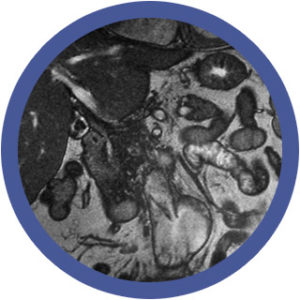

El diagnóstico por imagen del sistema nervioso central es una disciplina en constante evolución y de vital importancia para la práctica clínica. Por lo cual el conocimiento de una amplia variedad de patologías, desde tumores hasta accidentes cerebrovasculares, traumatismos craneoencefálicos y enfermedades neurodegenerativas, nos brinda habilidades para nuestra actividad laboral diaria.

La neuroimagen, como herramienta diagnóstica y de investigación, ha revolucionado nuestra comprensión del cerebro humano. Su aplicación en la práctica clínica ha permitido un diagnóstico más preciso y temprano de una amplia gama de enfermedades neurológicas, mejorando significativamente la atención al paciente.

Por otro lado, la evolución de las tecnologías de neuroimagen (RM, TC, PET, IA) ha ampliado considerablemente sus aplicaciones clínicas y de investigación. Así como también, la demanda de profesionales capacitados en neuroimagen ha aumentado considerablemente y que posean una formación sólida en los principios físicos, la anatomía, la fisiología y la patología del sistema nervioso central.

- Infecciones del sistema nervioso central.

- Tumores del SNC